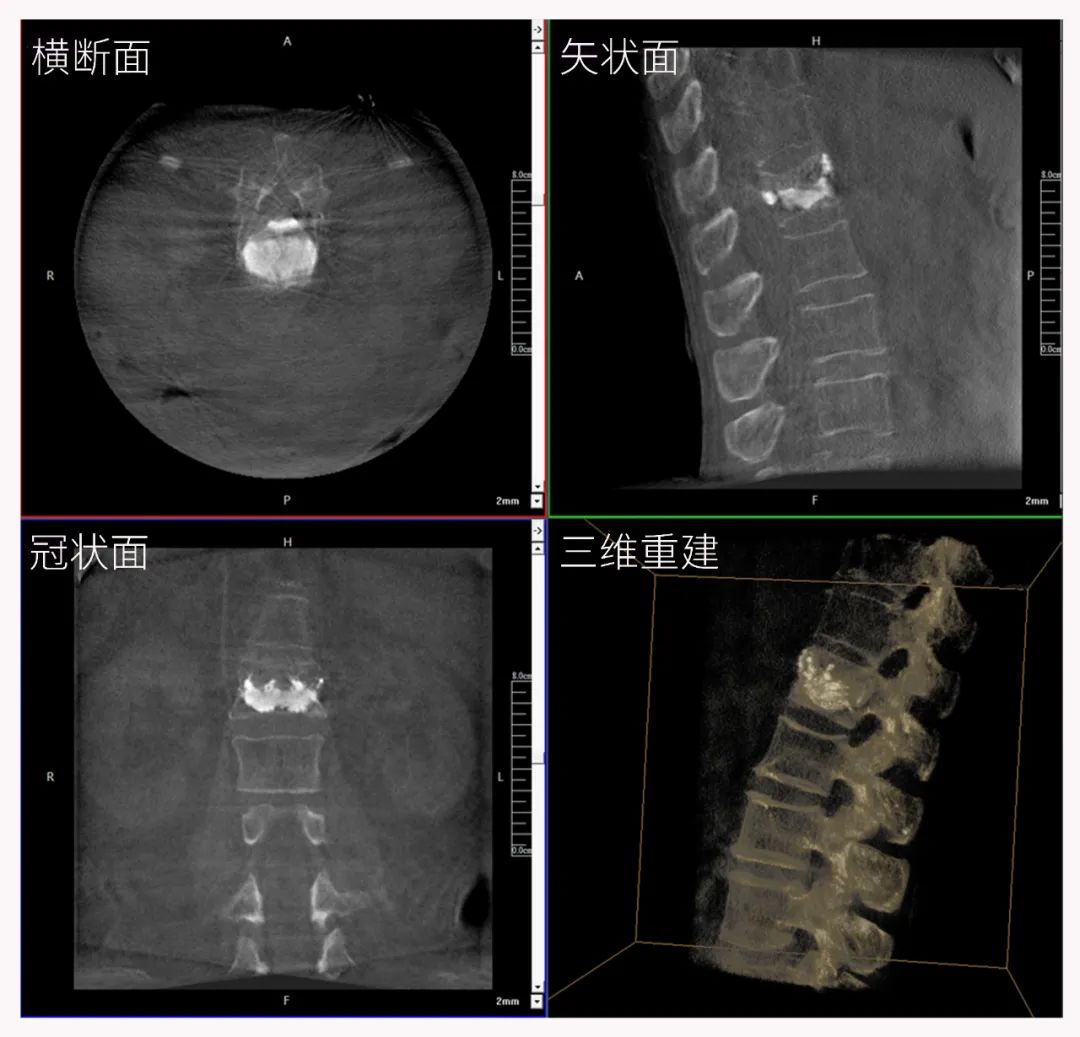

二維正側位影像

三維“類CT”影像

三維C形臂也被稱為“術中CT”,它具備二維C形臂的全部功能。此外,它還具備三維成像功能,三維C形臂旋轉采集多角度的二維投影數據,再通過計算機進行三維重建,能夠生成橫斷面、矢狀面、冠狀面斷層圖像以及三維立體圖像,提供更全面、更立體的解剖學信息。